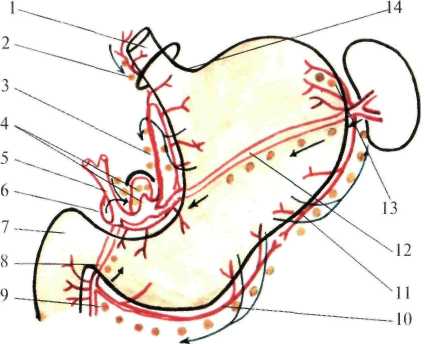

Лимфатические сосуды располагаются главным образом вдоль кровеносных сосудов желудка с регионарными лимфатическими узлами 1 порядка, в основном сконцентрированные в трех отделах: 1) по малой кривизне вдоль левой желудочной артерии; 2) у ворот селезенки и хвоста поджелудочной железы, принимает лимфу от левой трети дна и тела желудка до середины большой кривизны; 3) по ходу правой желудочной артерии вблизи привратника, принимает лимфу от правой половины большой кривизны желудка (рис.1.23).

От желудка лимфатические сосуды направляются через чревные узлы, расположенные возле чревного ствола. Кроме того, лимфатическая система желудка имеет многочисленные связи с соседними органами, что имеет большое значение в патологии органов брюшной полости.

Рис.1.23. Лимфоотгок желудка (схема).

1 — oesophagus; 2 — rami et nodi oesophagei; 3 — a. et nod. gastricae sinistrae; 4 — truncus et nodi coeliaci; 5 — a. et nod. hepaticae; 6 — a. et nod. gastricae dextrae; 7 — duodenum;

8 — a. gastroduodenalis et nod. retropyloricum; 9 — nod. subpyloricum; 10 — a. et nod. gastroomentales dextrae; 11 — a. et nod. gastroomentales sinistrae; 12 — a. et nod. splenici;

13 — a. et nod. gastricae breves; 14 — incisura cardiaca.